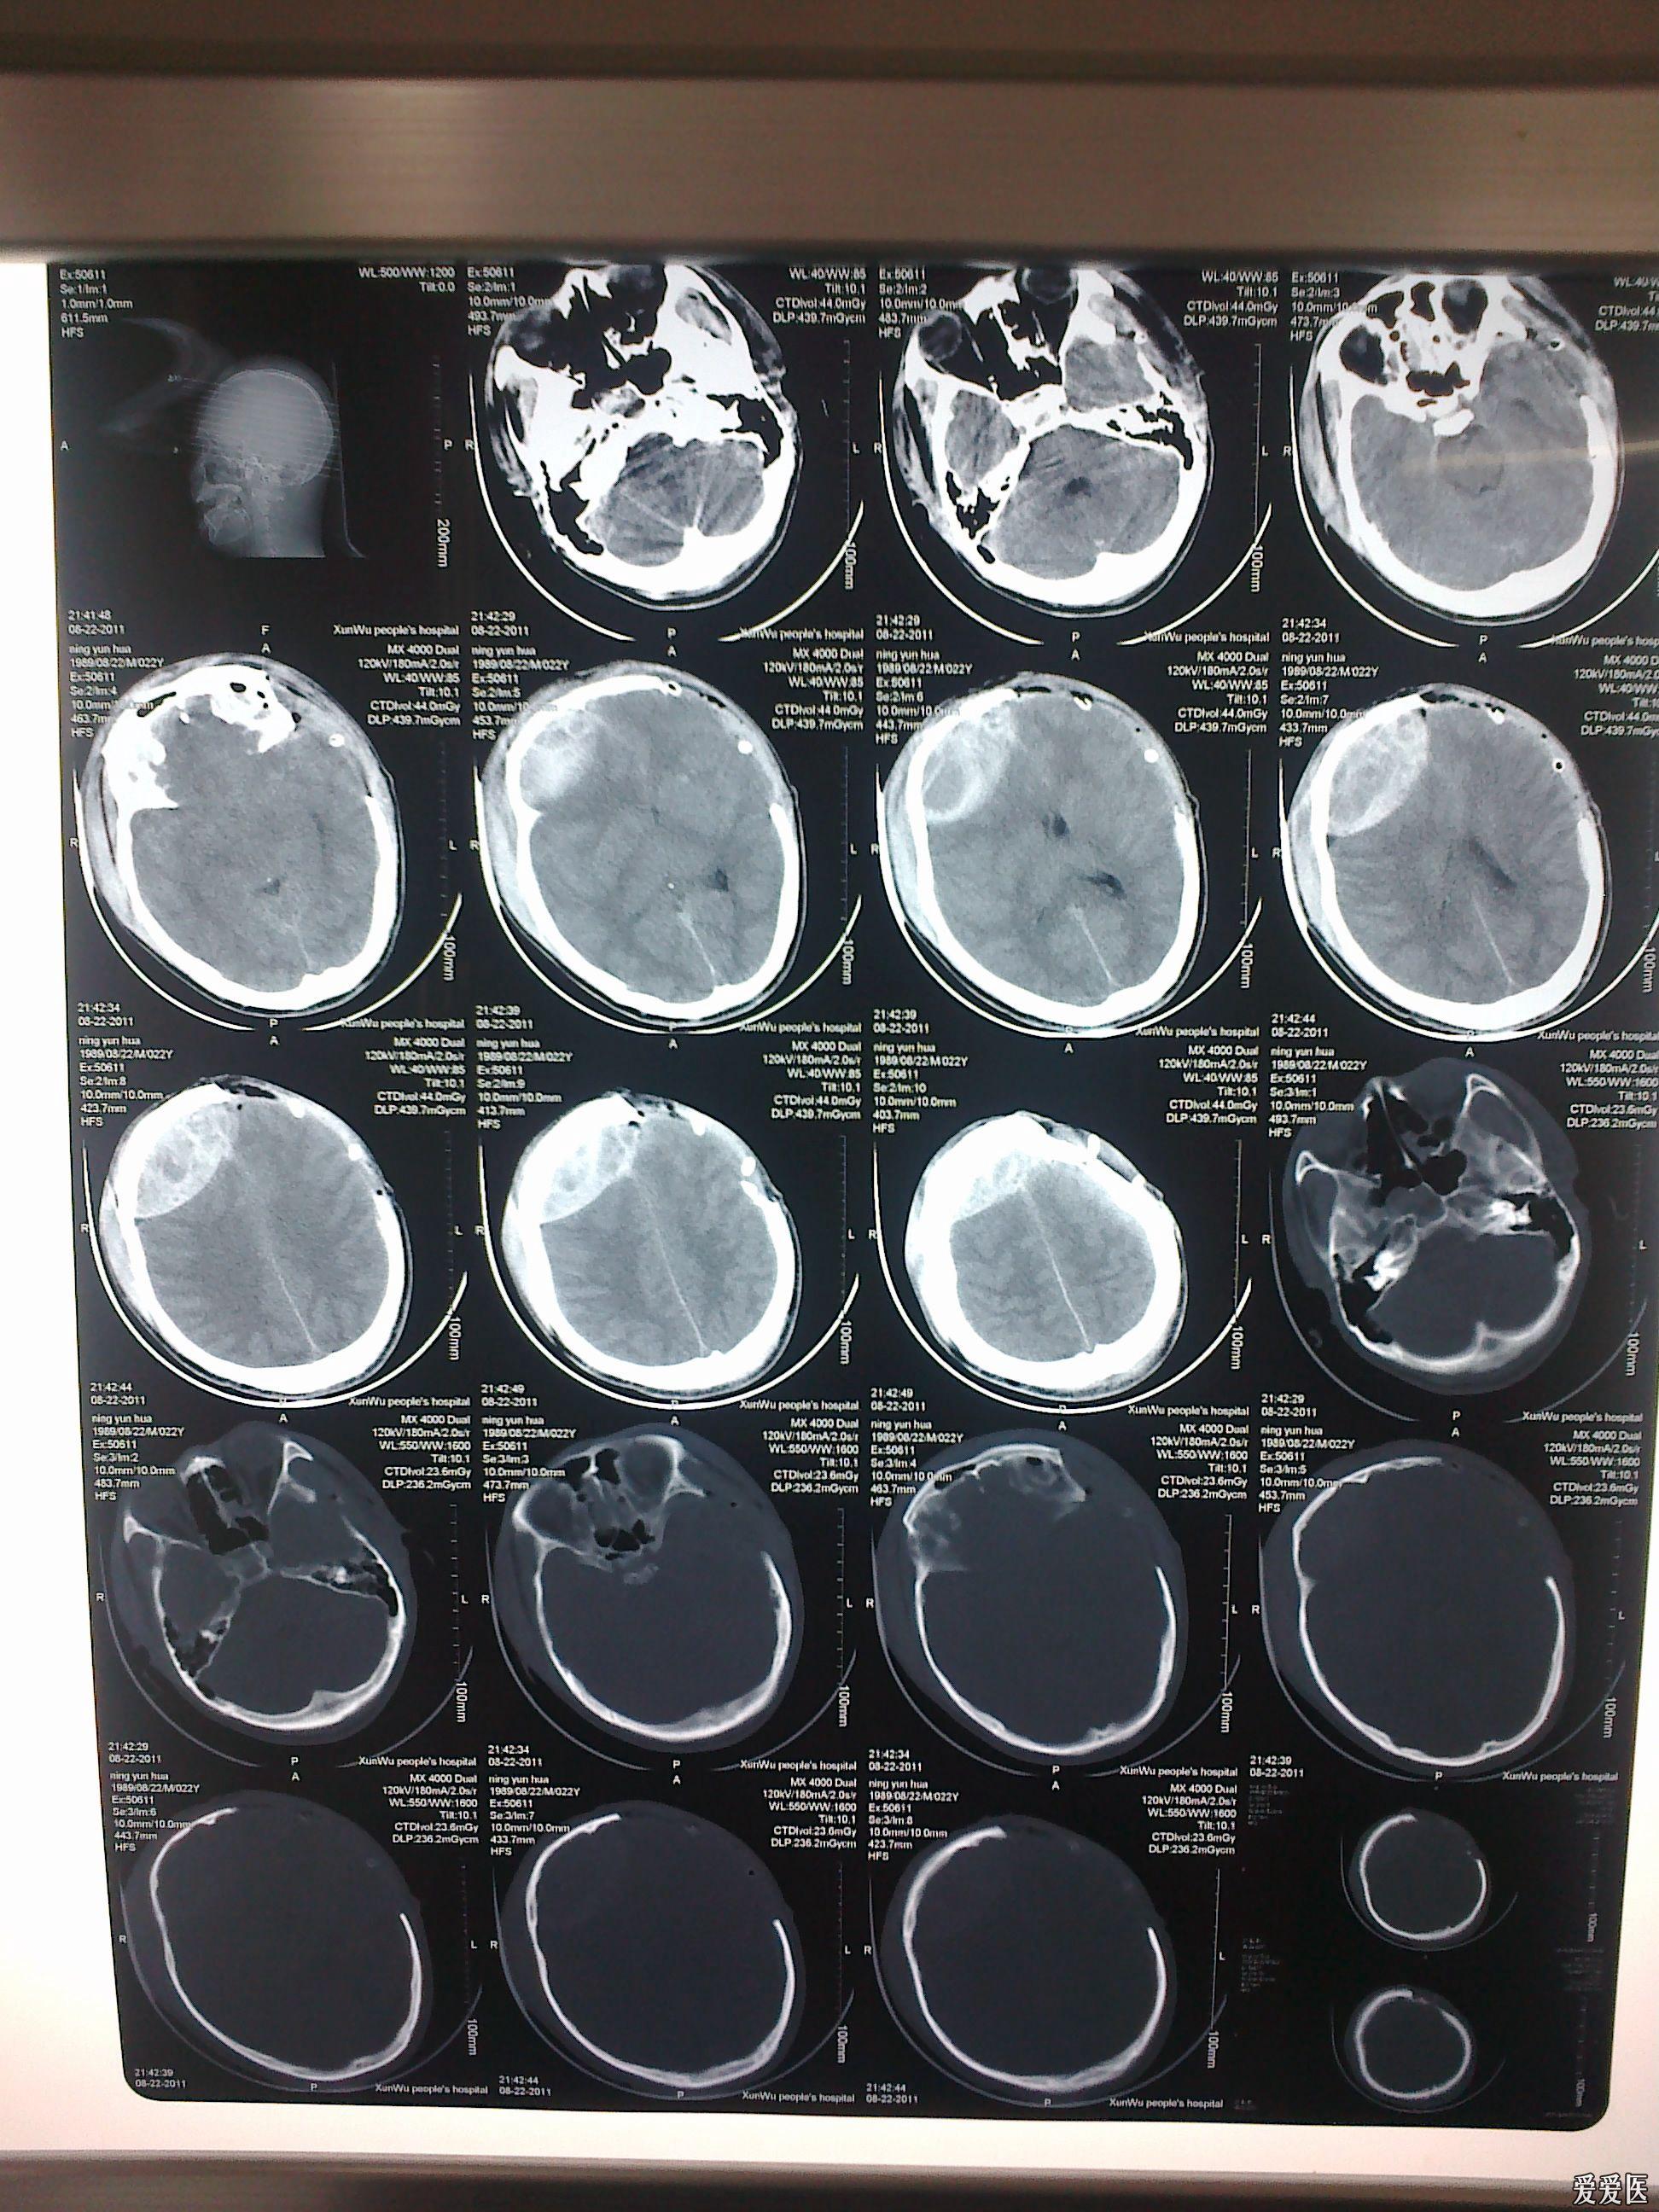

一例重度颅脑外伤患者的两面三刀

图片尺寸1944x2592